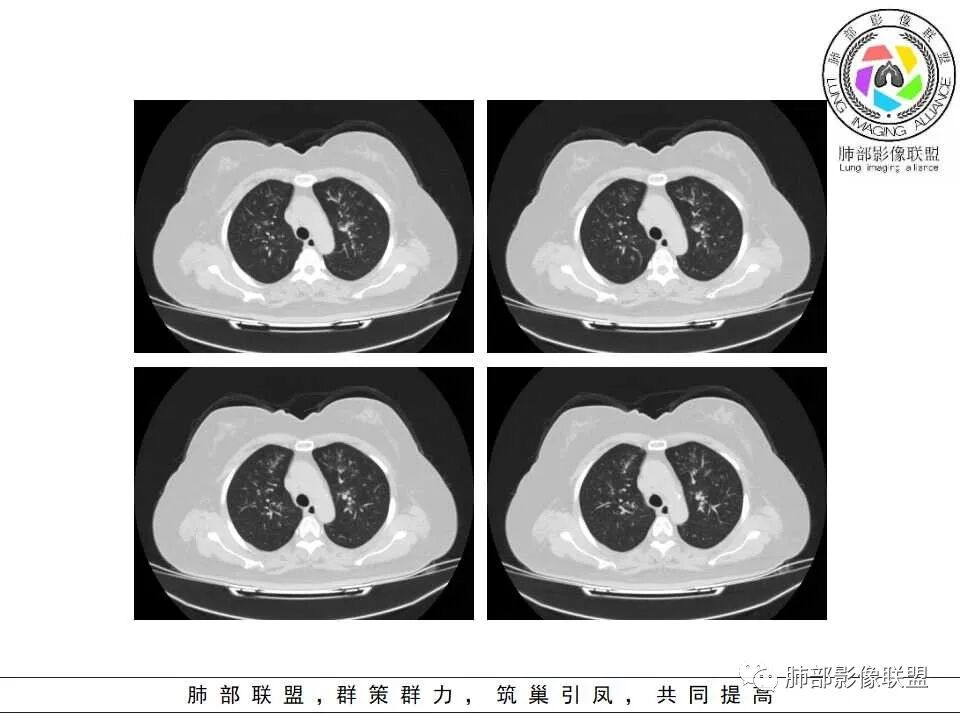

1.器官支气管管套样壁增厚和/或支气管扩张,注意壁增厚较均匀,和/或伴有播散性小片影及结节影,注意这些小片影或结节影边界有时较普通炎性病灶清楚。

2.可以阻塞支气管造成肺不张而酷似中央型肺癌。偶而可呈大范围毛玻璃样影。

3.易形成空洞,常无液平面。注意哪些一两周内出现的多发空洞病灶,形成空洞也往往靠边。

慢性病程,双肺支气管管壁增厚,周围可见多发点片状高密度影,边缘模糊不清,考虑气道侵袭性曲霉菌病

两肺支气管管壁增厚,沿支气管斑点状及斑片状高密度影,边缘模糊,考虑气道侵袭性曲霉菌,鉴别金葡萄、铜绿

居住地长年潮湿,老年女性,两肺支气管管壁增厚明显,考虑气道侵袭性曲霉菌,鉴别结核。

沿支气管血管束走形,气道壁增厚,边缘模糊,考虑考虑气道侵袭性曲霉,鉴别淋巴瘤。